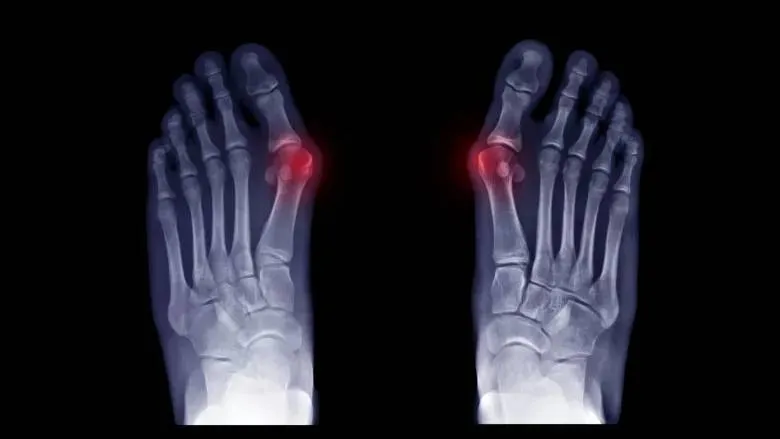

Pacienty přivádí k lékaři zejména bolesti v oblasti předonoží. Pokud jsou bolesti spojené se změnou postavení palce anebo s omezením jeho hybnosti, tak je tedy namístě navštívit ortopedickou ambulanci. Rentgenové snímky pak odhalí, v jakém stupni se onemocnění nachází. Velmi často se setkávám s pacientkami, které říkají, že předonoží je nebolí, protože omezily fyzickou aktivitu. Tento přístup není ale správný, protože fyzická aktivita je důležitá pro správou funkci nohy a pokud ji neprovádíme, tak se stav zhoršuje.

Existuje celá řada typů operací nohy. Tyto jsou nejčastěji založeny na korekčních osteotomiích první nártní kosti. Výraz osteotomie v názvu znamená protnutí kosti a korekční naznačuje vzájemný posun kostěných částí uvnitř nohy. Vzájemným posunem kostních fragmentů v noze se nastavují jiné mechanické poměry mezi klouby předonoží, a to vede k napřímení palce nohy. Podstatou moderních přístupů je ovlivňování předonoží tak, aby došlo nejenom k odstranění nevhodného postavení palce nohy, ale také aby byla odstraněna příčina vzniku deformity. Starší operační techniky pouze odstraňují kostěné výrůstky v okolí základního kloubu palce a často tak vedou k opětovnému rozvoji deformity do několika let po operaci.